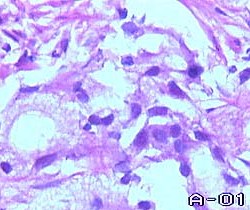

Своеобразным апофеозом злокачественности является недифференцированный рак. Эта гистологическая форма настолько атипична, что возникает необходимость дифференцировать ее с саркомами. Удивительное разнообразие клеточных форм и гистологических структур позволяет среди недифференцированного рака выделять такие подформы, как скиррозный рак (скирр). Эта опухоль представлена пластами соединительной ткани, в которой замурованы единичные эпителиоциты с яркими проявлениями клеточного атипизма. Также в соединительнотканных пластах можно обнаружить структуры, напоминающие мелкие ацинусы, либо сосочки переходного эпителия, а порой и небольшие пласты атипичного многослойного плоского эпителия.

Своеобразным апофеозом злокачественности является недифференцированный рак. Эта гистологическая форма настолько атипична, что возникает необходимость дифференцировать ее с саркомами. Удивительное разнообразие клеточных форм и гистологических структур позволяет среди недифференцированного рака выделять такие подформы, как скиррозный рак (скирр). Эта опухоль представлена пластами соединительной ткани, в которой замурованы единичные эпителиоциты с яркими проявлениями клеточного атипизма. Также в соединительнотканных пластах можно обнаружить структуры, напоминающие мелкие ацинусы, либо сосочки переходного эпителия, а порой и небольшие пласты атипичного многослойного плоского эпителия.

Однако клеточные элементы, составляющие эти скудные островки паренхимы, настолько атипичны, что сомнений в низкой степени их дифференцировки, как правило, не возникает.

Недифференцированный рак также может быть представлен миксоидноподобными структурами, когда среди моря слизи встречаются единичные мелкие, резко атипичные клетки. Но наиболее частый гистологический вид опухоли, составляют солидные разрастания резко атипичных клеток. Нередко среди них доминируют гигантские полигональные клетки с огромным гиперхромным ядром. В этих случаях речь идет о крупноклеточном раке. Однако, опухоль может быть представлена и мелкими мономорфными атипичными клетками. В этих случаях опухоль носит название мелкоклеточного рака. Если выделить доминирующую форму клеточных элементов не представляется возможным, а клеточные формы представляют самую причудливую гамму изменений, то опухоль диагностируется как полиморфноклеточный или саркомоподобный рак.